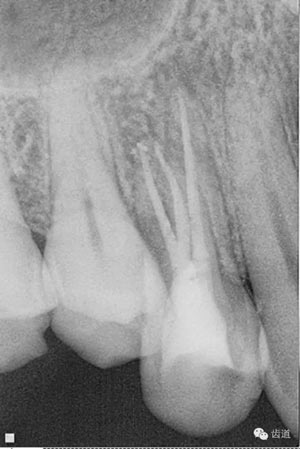

數(shù)碼攝影x片顯示:14遠(yuǎn)中鄰頜面暗影,穿髓。根尖暗影。無(wú)牙周膜增寬。

數(shù)碼x攝影顯示:近中頰根及腭根根管充填恰填,遠(yuǎn)中根管有遺漏。

檢查顯示:近頰及腭根充填恰填,遠(yuǎn)頰根管內(nèi)有少許充填物影像。根尖明顯低密度影像。